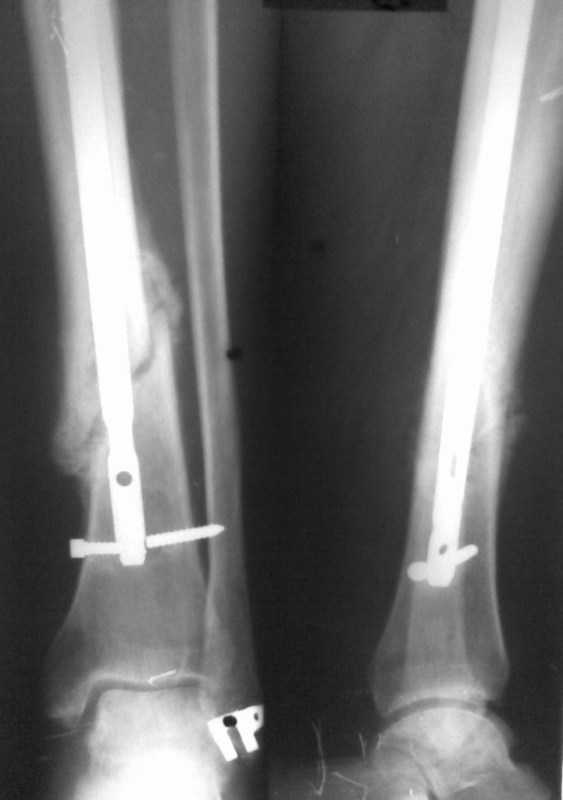

Больному произведено ОМС перелома голени блокирующим стежнем 2 мес. назад. Через 1 мес

больной начал наступать на ногу. В результате такая картина. Удален сломаный конец винта.

Интересует вопрос о дальнейшей тактике лечения. Кто может посоветовать как дальше

поступить. Оставить все как есть и приступать на ногу, провести замену стержня на другой или

поступить как-то иначе. Спасибо за советы и предложения